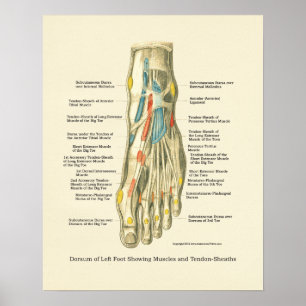

Poster interno da anatomia do pé & do tornozelo

Preço44,35 €

Poster da Anatomia Interna do Pé e Anca

Preço36,00 €

Poster da Anatomia Interna do Pé e Anca

Preço36,00 €